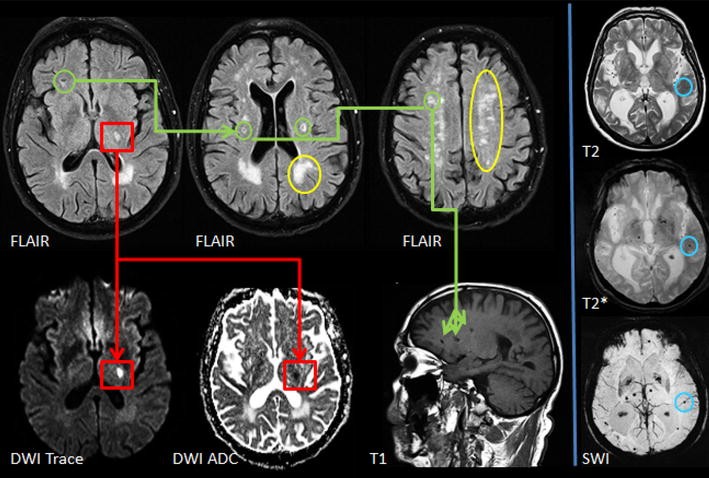

| Example Cases Of Cerebral Small Vessel Disease (CSVD) MRI A

| Example cases of Cerebral Small Vessel Disease (CSVD) MRI A www.researchgate.net

csvd vessel cerebral